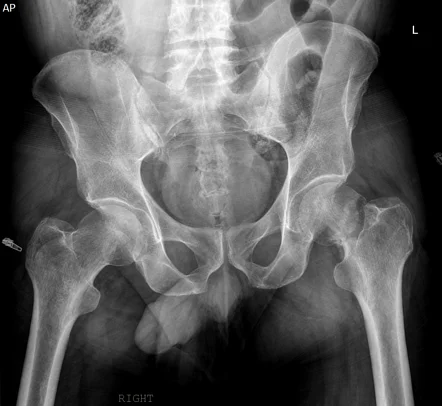

Types of hip fractures?

A hip fracture is a break in the upper portion of the femur (thigh bone), near the hip joint. These injuries most commonly occur in older adults, particularly those with osteoporosis or reduced bone density, but they can also result from high-impact trauma in younger patients, such as a car accident or significant fall.

Hip fractures are typically categorised based on the location and pattern of the break in the upper femur (thigh bone). Understanding the type of fracture helps guide the choice of surgical treatment and expected recovery pathway:

1. Intracapsular fractures

These fractures occur within the capsule of the hip joint, involving the femoral neck, which is the narrow section of bone just below the ball of the hip.